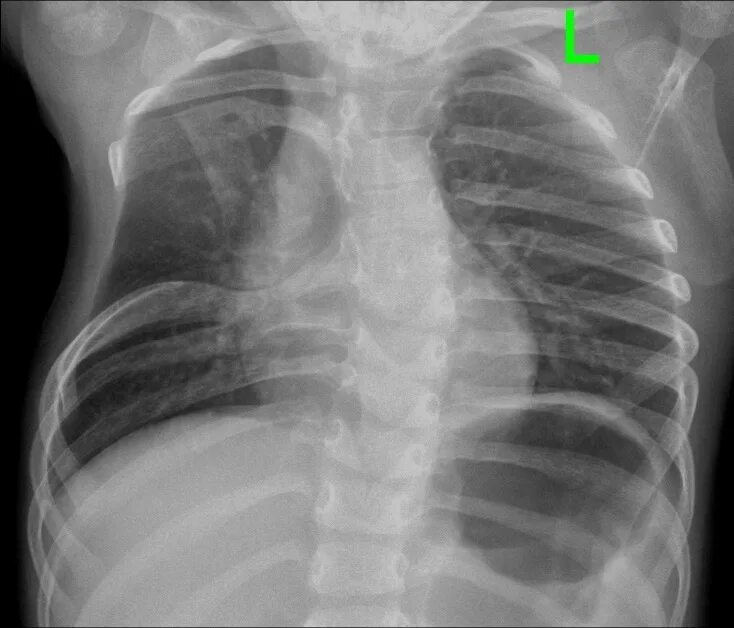

Мышечный дефект